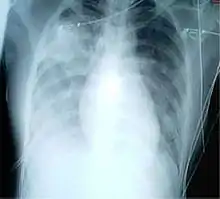

A chest X-ray showing increased opacity in both lungs, indicative of pneumonia, in a patient with SARS

For a case to be considered probable, a chest X-ray must be indicative for atypical pneumonia or acute respiratory distress syndrome.

The WHO has added the category of "laboratory confirmed SARS" which means patients who would otherwise be considered "probable" and have tested positive for SARS based on one of the approved tests (ELISA, immunofluorescence or PCR) but whose chest X-ray findings do not show SARS-CoV infection (e.g. ground glass opacities, patchy consolidations unilateral).[11][12]

The appearance of SARS-CoV in chest X-rays is not always uniform but generally appears as an abnormality with patchy infiltrates.[13]